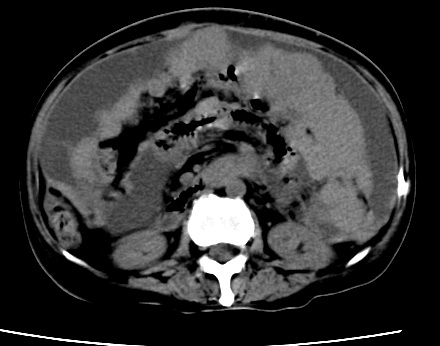

标题: CT23975:女61岁,腹部不适,明显消瘦

既往5年前卵巢癌行子宫及附件切除,右乳癌术后一年,考虑腹膜转移?

大量腹水,考虑腹膜转移。肝脏低密度灶。1囊肿,2转移。

支持楼主!(腹膜 网膜均有转移)

1)结合病史,考虑腹膜及网膜转移瘤。2)肝脏多发性低密度灶,不排除转移瘤。3)大量腹水。

考虑卵巢癌行子宫术后复发,并肝、腹腔 、大网膜转移可能性大。

大量腹水。